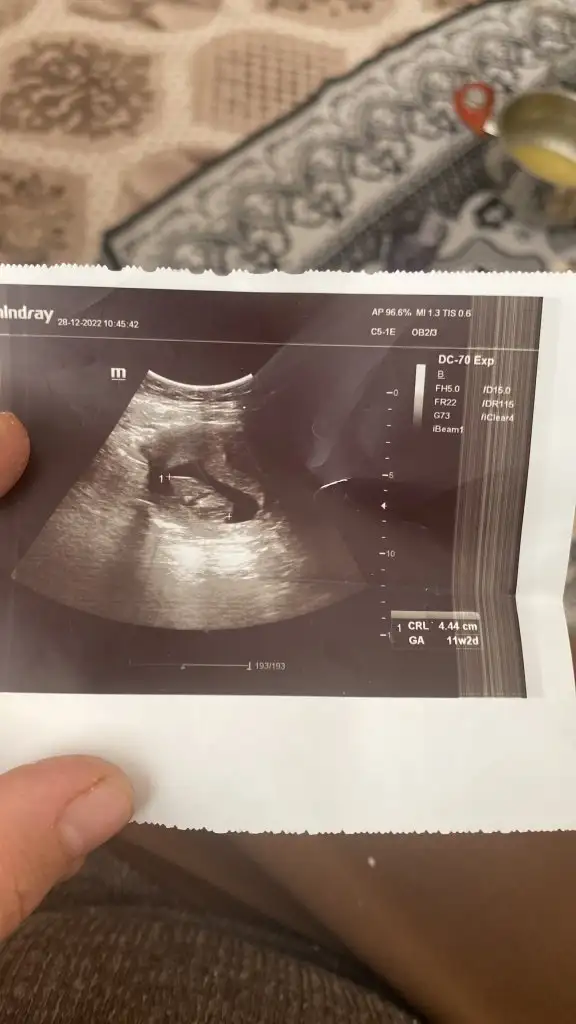

Bunu tahmin edebilir misin nuba göee 11+2

• 7DA7F9BC-DED7-46EC-BCE2-0F6AE7199860.webp

7DA7F9BC-DED7-46EC-BCE2-0F6AE7199860.webp

26,9 KB · Görüntüleme: 86